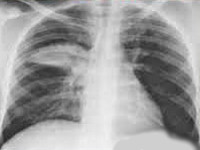

J16.0 Пневмония, вызванная хламидиями